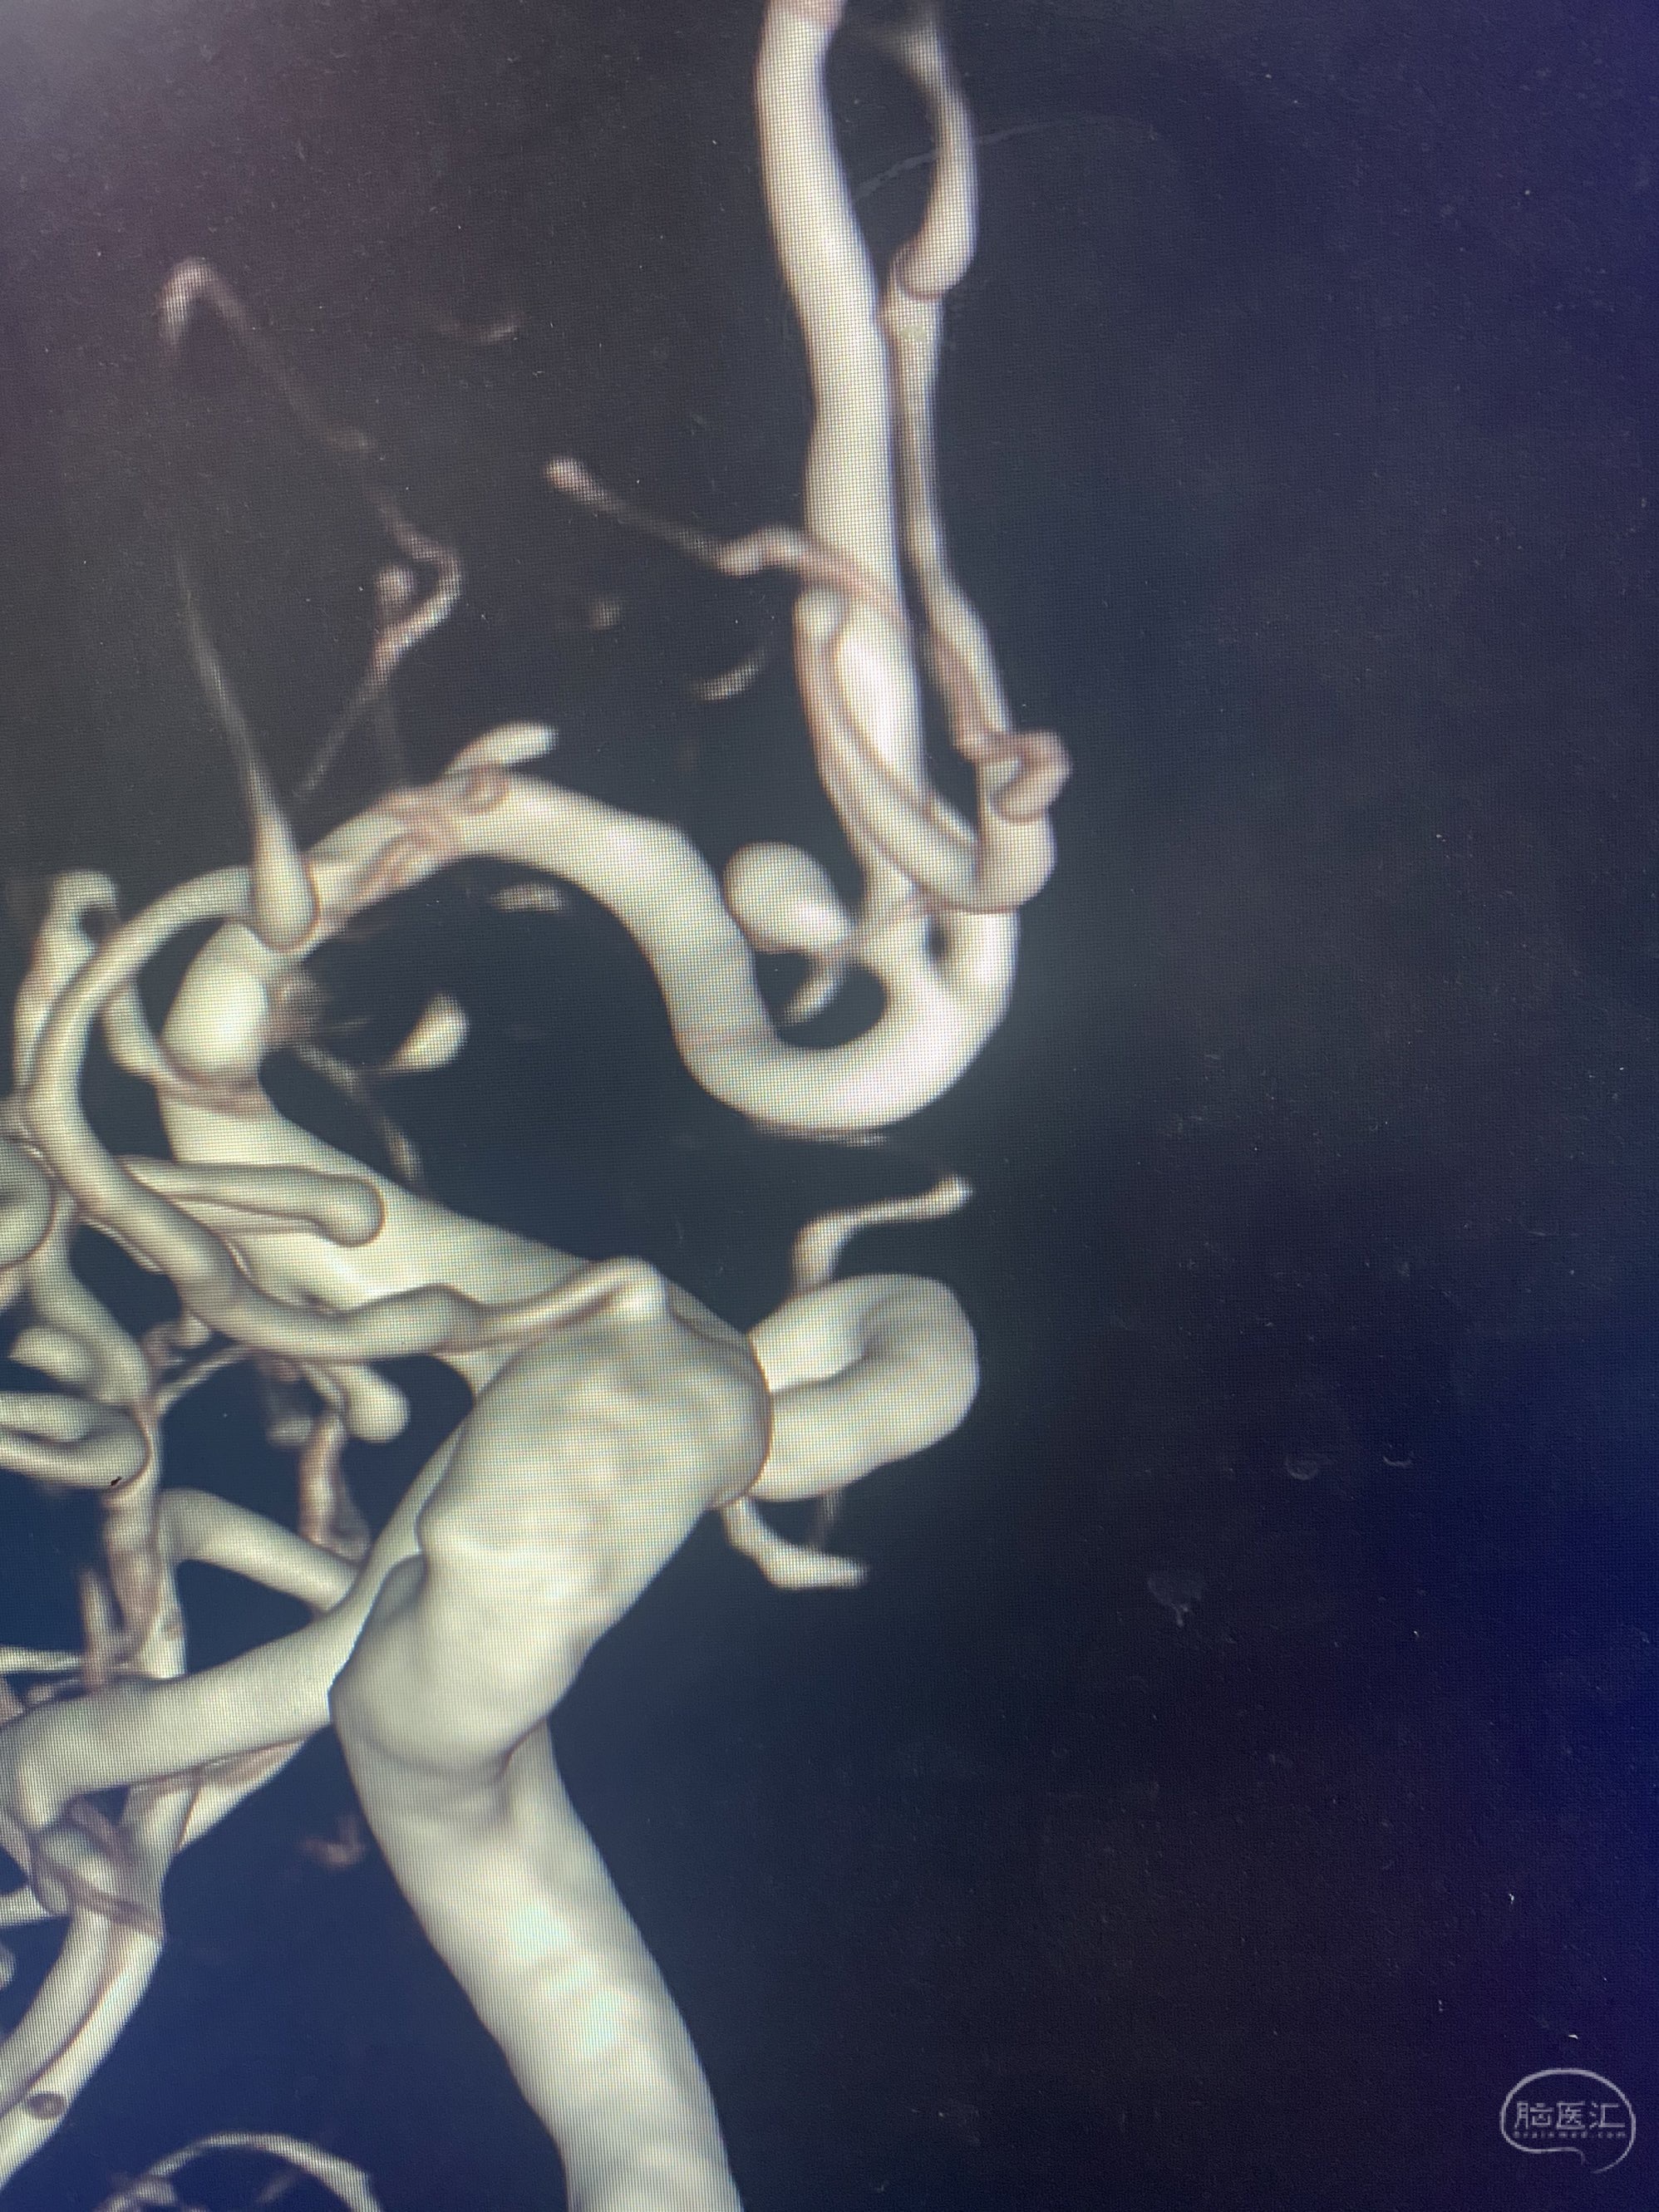

MLS,M79Y,sah,双侧MCA烟雾病,Heubner返动脉瘤,前交通段开窗,细支发出Heubner返动脉,瘤颈细长,瘤颈口比微导管细,弹簧圈2mmx3cm“隔山打牛”填塞治愈,Heubner返动脉保留。

Heubner返动脉是由大脑前动脉A1末端发出的豆纹动脉,由于走形和A1段相反,故称Heubner返动脉,该动脉梗塞可能引起尾状核头梗塞,引起偏瘫和面瘫,便身震颤等症状。